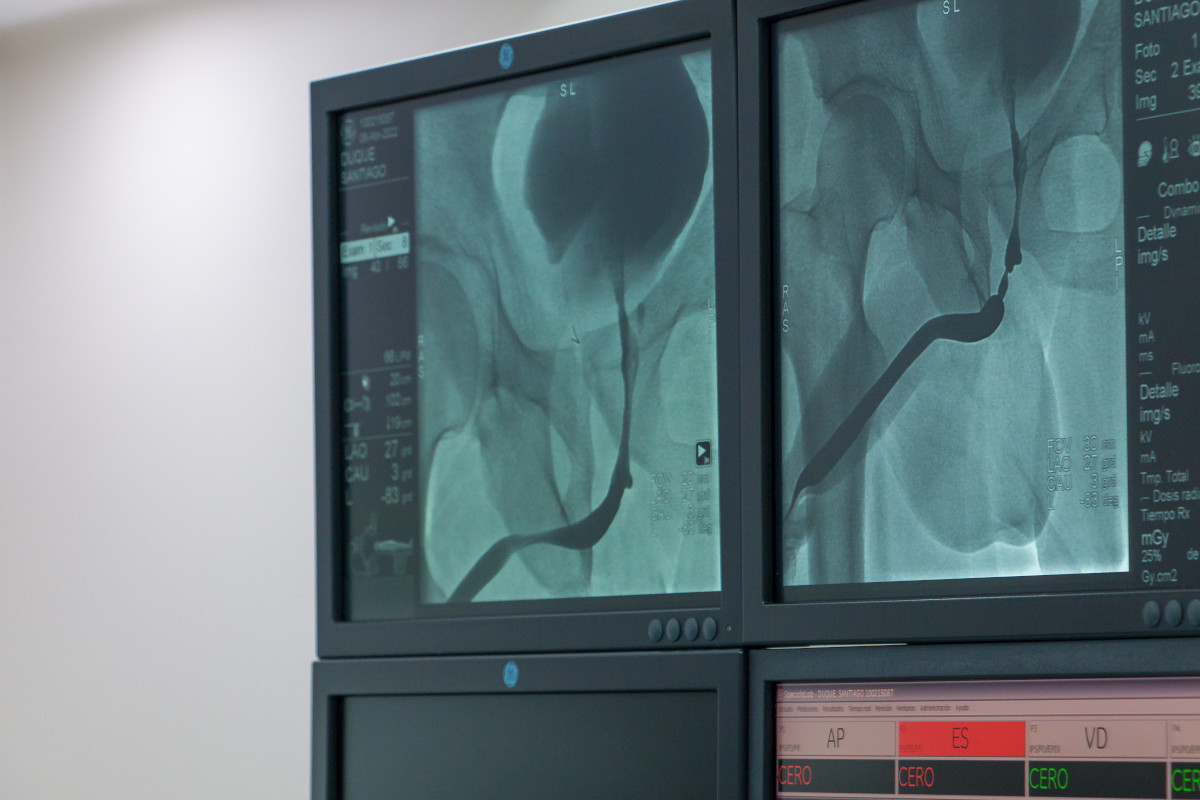

CAPACITACIÓN PROCEDIMIENTO URETRA

ABRIL 2022